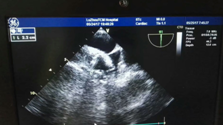

四、全程经食道心脏超声指引,让手术更精准。据朱彬介绍,特别值得一提的是,该手术是在我院开展的经食道心脏超声全程指引下完成,它是通过口腔植入超声探头,能全程直视左心耳及房间隔,具有封堵器释放更精准、明显降低手术风险等优势,大大提高了该手术的安全性和成功率。

术中经食道心脏超声指引